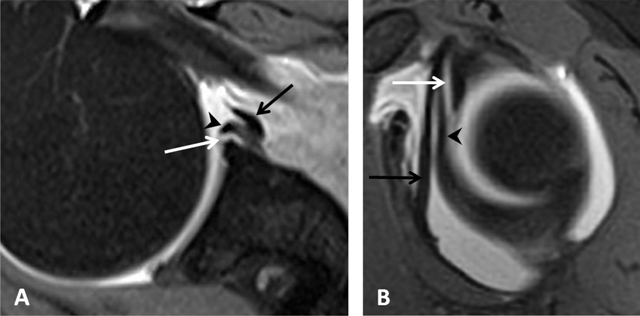

Figure 15

Buford complex. (A) Axial PD-weighted and (B) Sagittal fat-suppressed T1-weighted MR arthrographic images show a cord-like middle glenohumeral ligament (white arrow) associated with an absent anterior superior labrum (black arrow) mimicking a labral tear with normal posterior labrum. Subscapularis tendon (arrowhead). (Courtesy of Dr Henri Guerini).